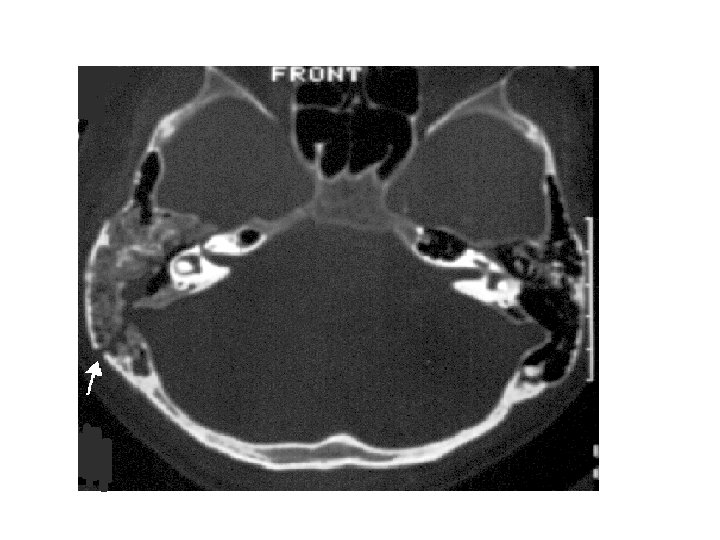

Fracture base